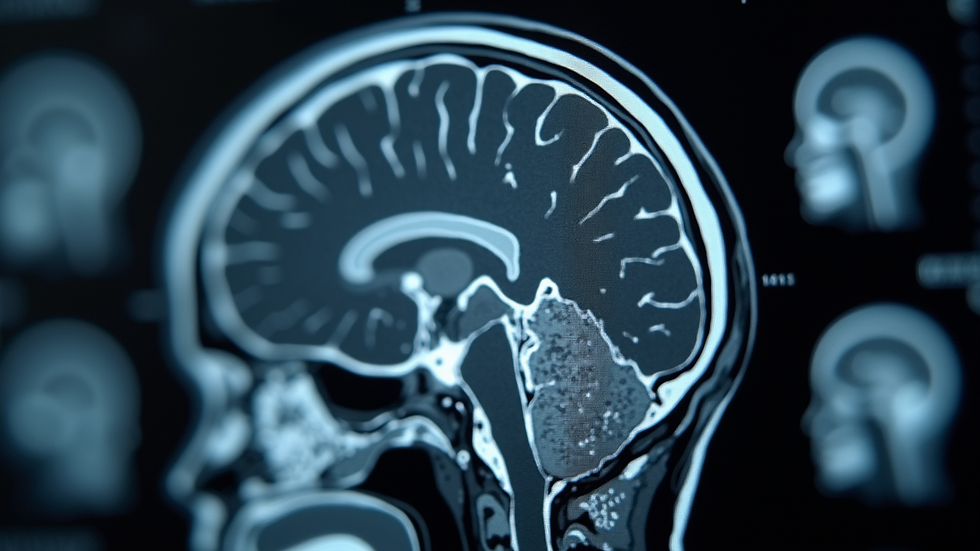

Neurological conditions affect the brain, spinal cord, and nerves. These conditions can cause a wide range of symptoms. They may include headaches, weakness, numbness, memory problems, or seizures. Understanding these conditions helps in managing them effectively. I will explain some key frequent neurological conditions and how they are managed.

Neurological disorders vary in severity and type. Some are chronic, while others may be acute or temporary. Common symptoms include pain, loss of function, or changes in sensation. Early diagnosis is important for better outcomes. Doctors use clinical exams, imaging, and tests to identify the condition.